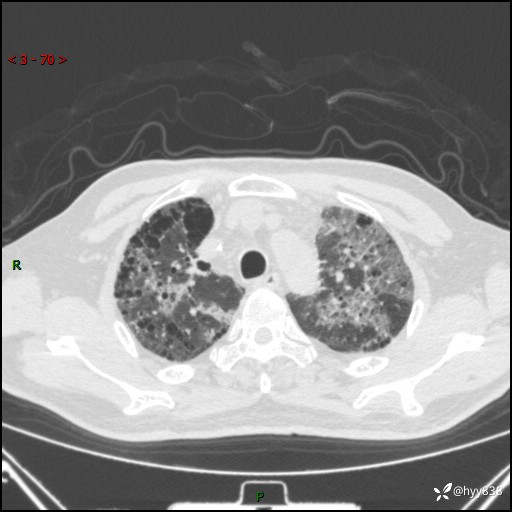

患者性别:男

患者年龄:64岁

简要病史:肝内胆管癌综合治疗后2周余,咳嗽、发热,咳白色泡沫痰。

临床诊断:感染?

讨论:病变性质?